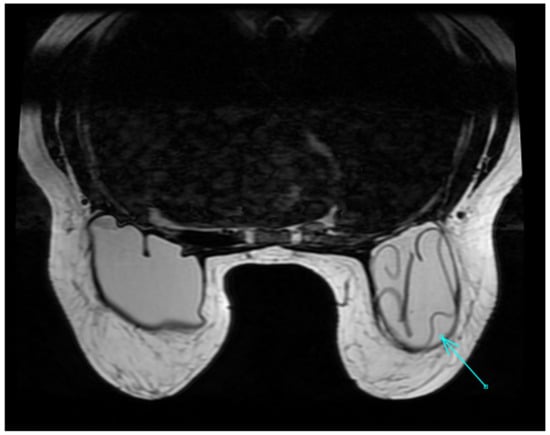

| MRI | Breast implants show different intensity signals due to their composition: -Silicone single lumen has an intermediate-to-high signal on T2W images, a high signal on the silicone-specific sequence, and a loss of signal in the silicone suppressed sequence; -Saline, single lumen has a high signal on T2W images; -Standard double lumen (outer saline, inner silicone); -Reverse double lumen (outer silicone, inner saline). A fibrous capsule hypointense in all sequences and a small periprosthetic fluid amount are paraphysiological findings. | Acute complications: -Hematoma —hyperintense on T1W images, decreasing over time; -Seroma—intermediate-to-hyperintense on T2W images; -Abscess—fluid collection with irregular, thick peripheral enhancement; -Ancillary signs—edema, skin thickening, and adenopathy. Late complications: -Capsular contraction—prosthetic contour alterations, peripheral enhancement; -Intracapsular breast implant rupture (uncollapsed rupture “keyhole sign”, minimal collapse “subcapsular line sign”, and partial-to-full collapse “linguine sign”); -Extracapsular breast implant rupture; -Rare, breast implant-associated anaplastic large-cell lymphoma, ALCL (peri-implant collection with an enhancing mass and lymphadenopathy). | Breast magnetic resonance imaging is the most accurate technique to assess prosthetic integrity in the clinical or ultrasound suspicion of rupture, but is not justified as a pure screening examination in asymptomatic women of all ages and with any type of prosthesis. Its parametric nature allows the typing of the content of periprosthetic fluid collections (seroma, hematoma) and, combined with the administration of contrast medium, the detection of periprosthetic neoplastic recurrences or complications (breast implant-associated anaplastic large-cell lymphoma, ALCL). |